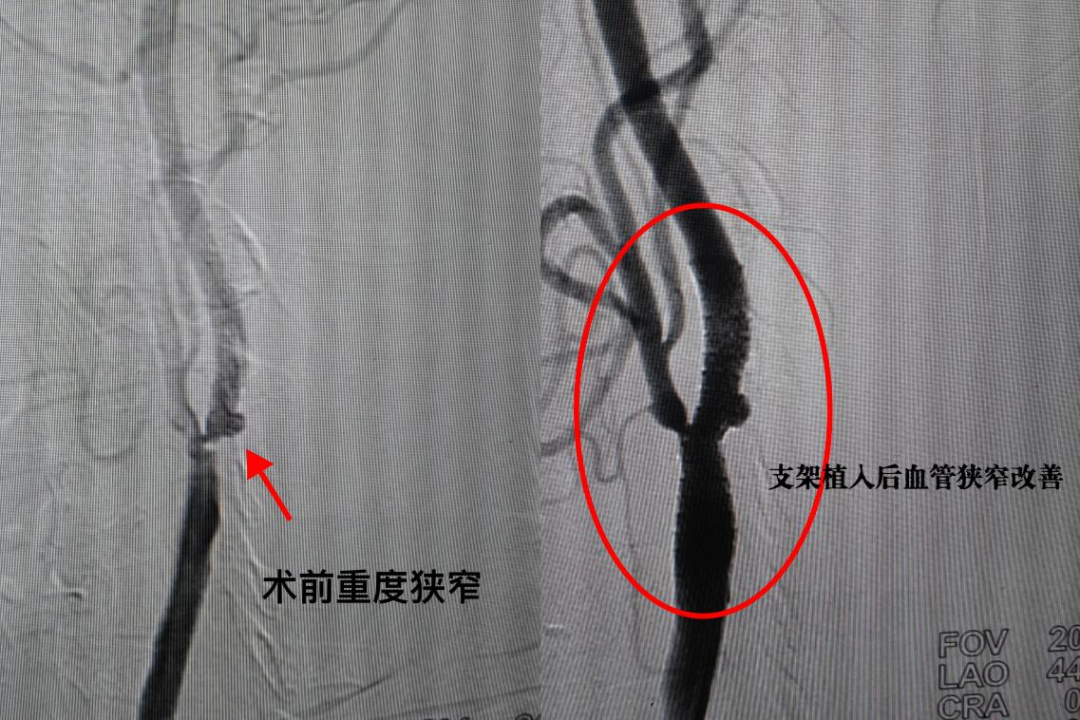

近一周症状明显加重后,家属担心不已,再次带罗大姐迈上求医路。多方打听后,就诊于福建医科大学附属协和医院脑血管病科,完善相关检查发现,罗大姐双侧颈内动脉重度狭窄伴急性脑梗塞。经过详细评估后,陈文伙主任考虑罗大姐为颈内动脉狭窄导致的颅内供血不足。

陈主任评估病情,并和罗大姐商量后,决定为罗大姐选择创伤小,耐受性好的经桡动脉入路脑血管成型术。在手臂上开一个小口,局麻下行颈动脉狭窄球囊扩张加支架植入术,短短数十分钟恢复了罗大姐颅内血供。手术效果立竿见影。术后,罗大姐即刻下地,行走自如。